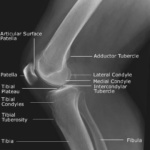

Las radiografías, generalmente llamadas rayos X, producen imágenes como sombras de huesos y ciertos órganos y tejidos. Las radiografías son muy buenas para detectar problemas óseos. Pueden mostrar algunos órganos y tejidos blandos; sin embargo, la MRI y la CT suelen crear mejores imágenes de los mismos. Aun así, las radiografías son rápidas, fáciles de obtener y menos costosas que los otros estudios, por lo que se pueden usar para obtener información rápidamente.

Un tubo especial dentro de la máquina de rayos X emite un haz de radiación controlada. Los tejidos del cuerpo absorben o bloquean la radiación en diferentes grados. Los tejidos densos como los huesos bloquean la mayor parte de la radiación, pero los tejidos blandos, como la grasa o los músculos, bloquean menos radiación. Después de pasar por el cuerpo, el haz alcanza una pieza de un fragmento de película o un detector especial. Los tejidos que bloquean altas cantidades de radiación, como los huesos, aparecen como áreas blancas en un fondo negro. Los tejidos blandos bloquean menos radiación y aparecen en tonos de gris. Los órganos que contienen principalmente aire (como los pulmones) aparecen en negro. Los tumores son por lo general más densos que el tejido que los rodea, por lo que suelen verse en tonos grises más claros.